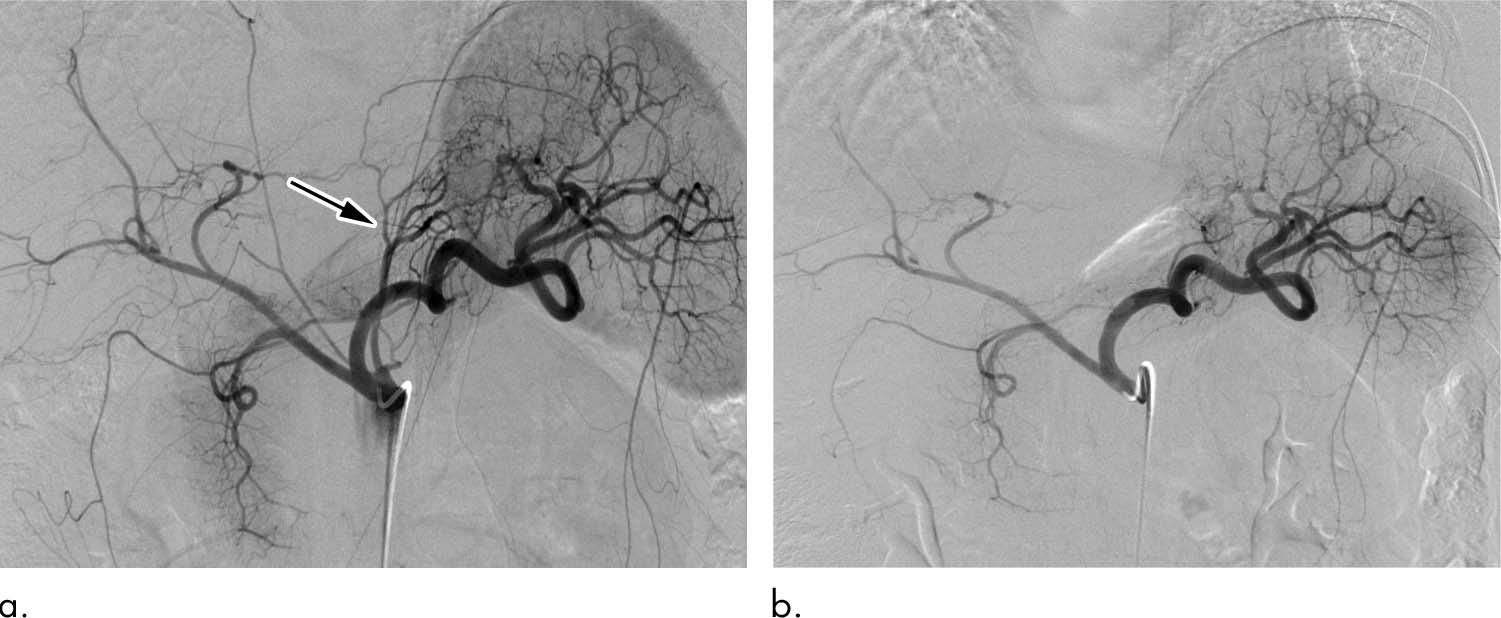

Bariatric embolization has emerged in recent years as one such option. In the procedure, microscopic spheres are introduced through a catheter into the arteries that supply blood to the stomach. The blocking of the arteries with the beads produces a reduction in blood flow—enough to suppress production of hunger-stimulating hormones but not enough to cause tissue damage.